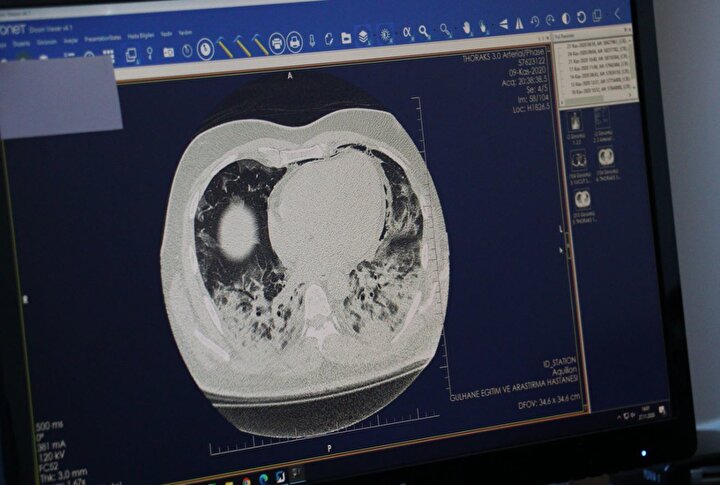

Koronavirüs salgınının çok ciddi anlamda hasara yol açtığı ve kişide solunum yetmezliğine giden sürecin kapısını araladığı akciğerdeki tahribatın görüntüleri yayımlandı. Doç. Dr. Cantürk Taşçı, ''Covid-19, akciğerdeki solunum keseciklerinde hasara yol açıyor. Orada bir sertleşme, büzüşme, solunum keseciklerinin fonksiyonlarını yitirmesine neden oluyor. Bu, yaygınlığı, şiddeti arttıkça hastaları solunum yetmezliğine götürebiliyor" dedi.

Doç. Dr. Taşçı, bir kısım hastalarda, özellikle daha yaşlı olan hastalarda ve genç hastaların da bir kısmında virüsün üst solunum yolundan girdikten sonra alt solunum yollarına geçtiğine işaret ederek, "Burada o bildiğimiz zatürremsi olaya yol açmakta, bundan sonraki süreç hastadan hastaya değişmekte. Virüsün seyri ile beraber ilk 3-4 gün biraz daha farklı olmakta. Hastalığın ilk semptomlarının başlamasından 8-12'nci gün arası ciddi bir alevlenme yaşayabilmekteyiz. Ancak bu da dediğim gibi her hastada değil, o süreçte hastalara müdahale ederek tedavisini düzenlemekteyiz" diye konuştu.Doç. Dr. Taşçı, koronavirüsün akciğerdeki solunum keseciklerinde hasara yol açtığını kaydederek, "Orada bir sertleşme, büzüşme, solunum keseciklerinin fonksiyonlarını yitirmesine neden oluyor. Bu, yaygınlığı, şiddeti arttıkça hastaları solunum yetmezliğine götürebiliyor. Ama dediğim gibi her hastada farklı seyretmekte. Hastanın kendi bağışıklık sisteminin gücüyle beraber bazı hastalarda solunum yetmezliğine, bir kısım hastada yoğun bakıma kadar ilerleyebilmekte. Bazı hastalarda çok yaygın akciğer büzüşmesi denilen tabloya yol açıyor. Tabii ki bu hastaları biz yine iyileştiklerinde taburcu ediyoruz; ama akciğerdeki düzelmeler akciğer büzüşmesi oluştuysa ayları bulabiliyor. Onun dışında o kadar şiddetli değilse taburcu olduktan yaklaşık 1 hafta 10 gün sonra akciğerleri tamamen normale de dönebiliyor. Akciğerde kalıcı hasar şu ana kadar gördüklerimizde yok. Hastaları kontrollere çağırıyoruz, akciğer hasarı takiplerimizde hemen hemen yok" ifadelerini kullandı.